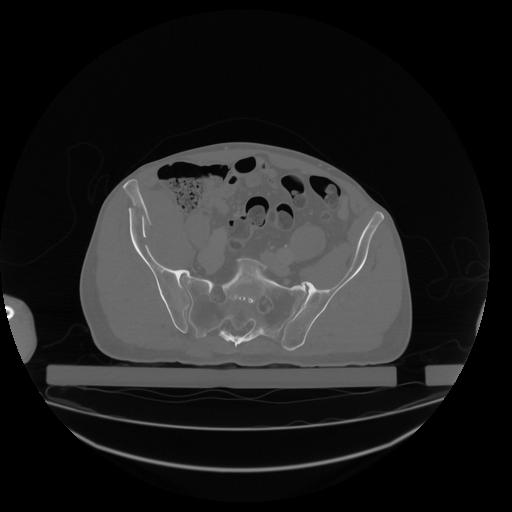

34 CUERPO,CE,Vol,1.0,CUERPO,,